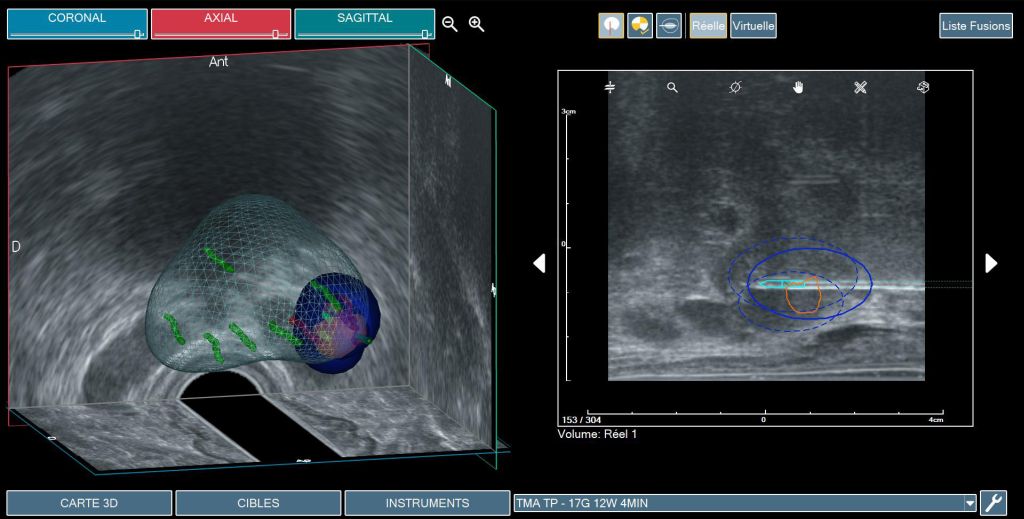

TMA (Targeted Microwave Ablation) to mikrofalowa terapia celowana, w której wykorzystywane są te same modele wirtualne prostaty, jakie stosujemy w biopsji fuzyjnej. W praktyce oznacza to, że lekarz trafia dokładnie w ten sam punkt, z którego wcześniej pobierał wycinek do postawienia diagnozy – tyle że zamiast pobierać próbkę, wprowadza igłę emitującą mikrofale. W taki wysoce precyzyjny sposób, przy wykorzystaniu TMA, niszczy się komórki nowotworowe.

- TMA opiera się na danych z rezonansu magnetycznego, który był wykonany wcześniej i pod kontrolą nawigacji przestrzennej jest w stanie trafić w ściśle określony nieduży punkt, tzn. ognisko raka w prostacie. Dzięki temu oddziaływanie jest tylko na to konkretne miejsce, które stanowić może zaledwie kilka procent całej prostaty, ale w którym znajduje się rak istotny klinicznie.